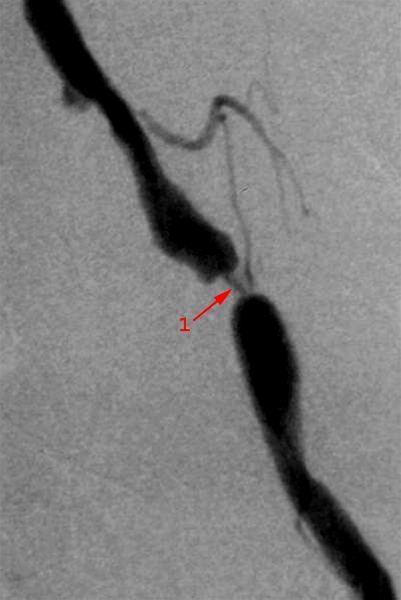

Arteriografi med røntgenkontrastvæske i venstre bækkenpulsåre

Kort, tæt stenose (forsnævring) i bækkenarterie (1).

Forsnævringen vil kunne behandles med udblokning med ballon og evt. indsættelse af et metaltnetværk (stent).